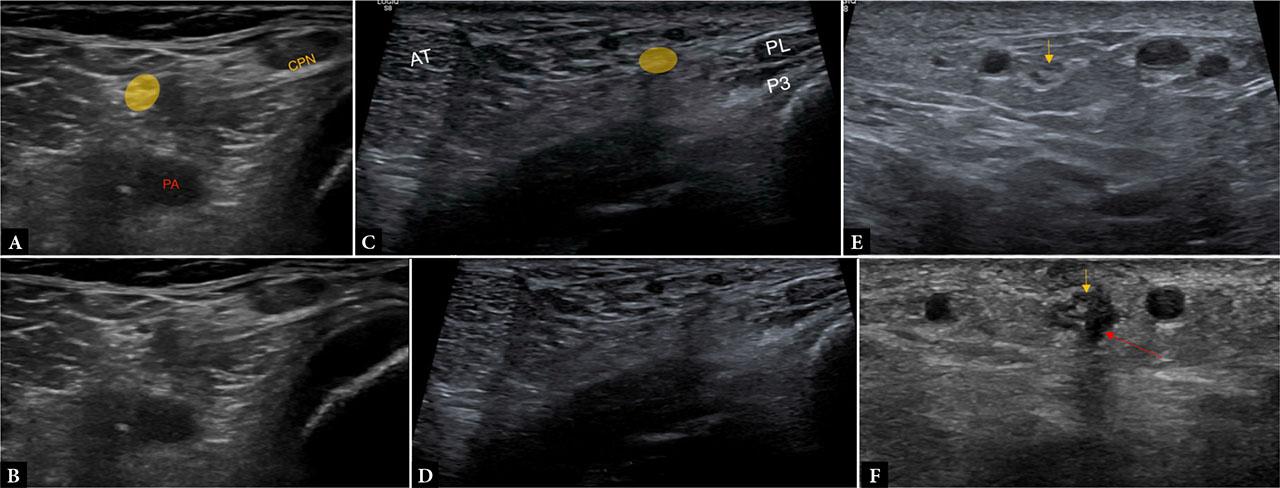

The sural nerve, formed by contributions from the tibial and common peroneal nerves, runs with the small saphenous vein along the posterior calf and ankle. The lateral sural nerve arises at the level of the popliteal fossa from the common peroneal nerve, proximal to the fibular head. Ultrasound reliably demonstrates the sural nerve as a hypoechoic fascicular structure lateral to the Achilles tendon in the lower leg, and it can be traced proximally from this site as it lies superficial to the gastrocnemius muscle bellies. Because of its superficial location, the sural nerve is prone to iatrogenic injuries in procedures around the ankle, and pre-procedural sonographic mapping can help reduce such complications(20) (Fig. 12).

Images A and B demonstrate the origin of the sural nerve (yellow) in the lateral aspect of the popliteal fossa from the common peroneal nerve (CPN). Here, the CPN is thickened, while the sural nerve remains normal in caliber and echogenicity. Images C and D demonstrate the sural nerve (yellow) at the level of the lateral ankle within the subcutaneous plane between the Achilles tendon (AT) and the peroneal tendons (PL/PB). Image E demonstrates edema within the sural nerve (yellow arrow) in the distal leg, and image F demonstrates a partial neuroma in the sural nerve (yellow arrow) at the level of the ankle following arthroscopy. The red arrow demonstrates the portal site and route, coursing along the lateral margin of the nerve, resulting in partial epineurial disruption

The superficial peroneal nerve arises from the common peroneal nerve, becoming superficial in the distal third of the leg before dividing into dorsal cutaneous branches. It is visualized as it emerges between the peroneus longus and brevis muscles and pierces the crural fascia. Variations in the fascial exit point are common and may predispose to entrapment neuropathy, particularly in athletes and patients with chronic ankle instability. Ultrasound is valuable both for diagnosis – demonstrating focal nerve enlargement or hypoechogenicity at the fascial penetration site – and for guiding therapeutic hydrodissection or perineural injections(2,22,23,24) (Fig. 13).

Images A and B demonstrate the normal superficial peroneal nerve (yellow) in the mid-lower leg as it pierces the lateral muscular septum, with underlying lateral muscle bellies (M). Image C shows a peripheral nerve sheath tumor involving the superficial peroneal nerve (arrows)